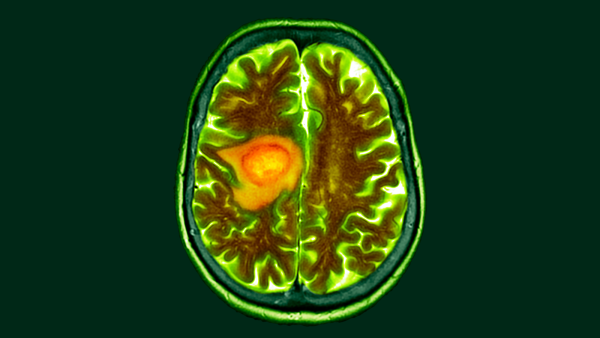

Дослідники хотіли з'ясувати, чи призводять ці структурні зміни, викликані доцетакселом, до погіршення пам'яті чи змін у поведінці. Вони виявили, що здорові миші, яких лікували доцетакселом, забували об'єкти, які вони бачили раніше, тоді як неліковані миші демонстрували чіткі ознаки їх запам'ятовування. МРТ-сканування оброблених мишей показало, що ці когнітивні проблеми корелюють зі зниженням потоку рідини через лімфатичні судини, пишуть автори в дослідженні.